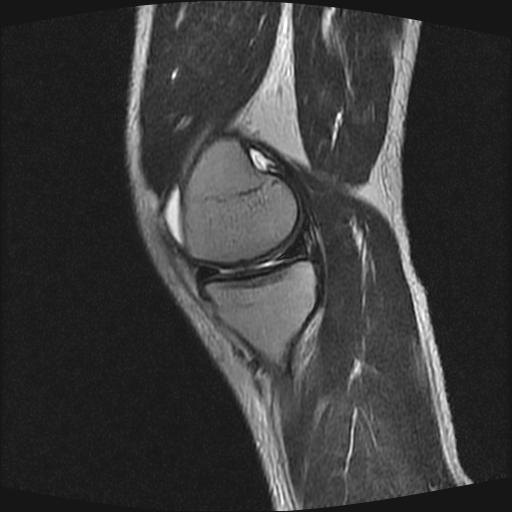

40岁男性,右膝关节外伤,x光平片示,髁间隆突撕脱骨折。

1、前交叉韧带撕裂;

2、外侧半月板后角撕裂;

3、关节腔积液。

前交叉韧带撕裂,关节腔积液.

半月板1-2级损伤   前交叉韧带撕裂伤   关节腔少量积液  诸骨未见新鲜外伤性改变

髁间隆突撕脱骨折;内侧副韧带损伤。

1、内侧副韧带撕裂;

2、前交叉韧带撕裂;

3、滑膜炎伴关节腔积液。

内侧副韧带撕裂及关节腔积液是肯定的,但是前交叉撕裂确定吗?会不会有容积效应的因素,因为前一张前交叉显示清楚,连续性良好,且较光滑。请问楼主有关节镜支持吗?我们医院也经常有这样的患者,但苦于没有关节镜,而无法对照、证实(除非完全断裂),出现了不同的诊断结果只能毫无意义的争论。

1、前交叉韧、内侧副韧带撕裂;

3、关节腔积液。4、髁间脊撕脱骨折。